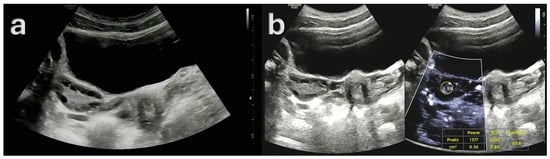

- Gray-Scale Ultrasonography (USG): A Samsung RS85 Prestige Ultrasound System (Samsung Medison) with a convex transducer (CA1-7A, 1–7 MHz) was utilized to perform gray-scale ultrasonographic assessment. The evaluation of each ovary involved a systematic examination for polycystic ovarian morphology (PCOM). This condition was characterized by either the presence of 20 or more follicles with diameters ranging from 2 to 9 mm, or an ovarian volume greater than 10 cm3.

- Doppler Examination (MV-Flow, MVI): Ovarian stromal vascularity was evaluated using the same ultrasound equipment and transducer (Samsung RS85 Prestige with CA1-7A, 1–7 MHz). MV-Flow Doppler imaging was performed consistently in the longitudinal plane to maintain anatomical standardization. Cine-loop clips of at least 3 s duration were captured and stored. For vascularity index measurements, the optimal frame demonstrating clear vascular flow was selected from the stored cine-loop clips. In the ovarian stroma, three circular regions of interest (ROIs) were centrally positioned. These ROIs, each with a fixed 5 mm diameter, were carefully selected to exclude dominant follicles and peripheral vascular structures. The ROI dimensions and MV-Flow Doppler imaging parameters, including pulse repetition frequency (PRF), gain, and wall filter, were maintained consistently throughout the duration of the study.